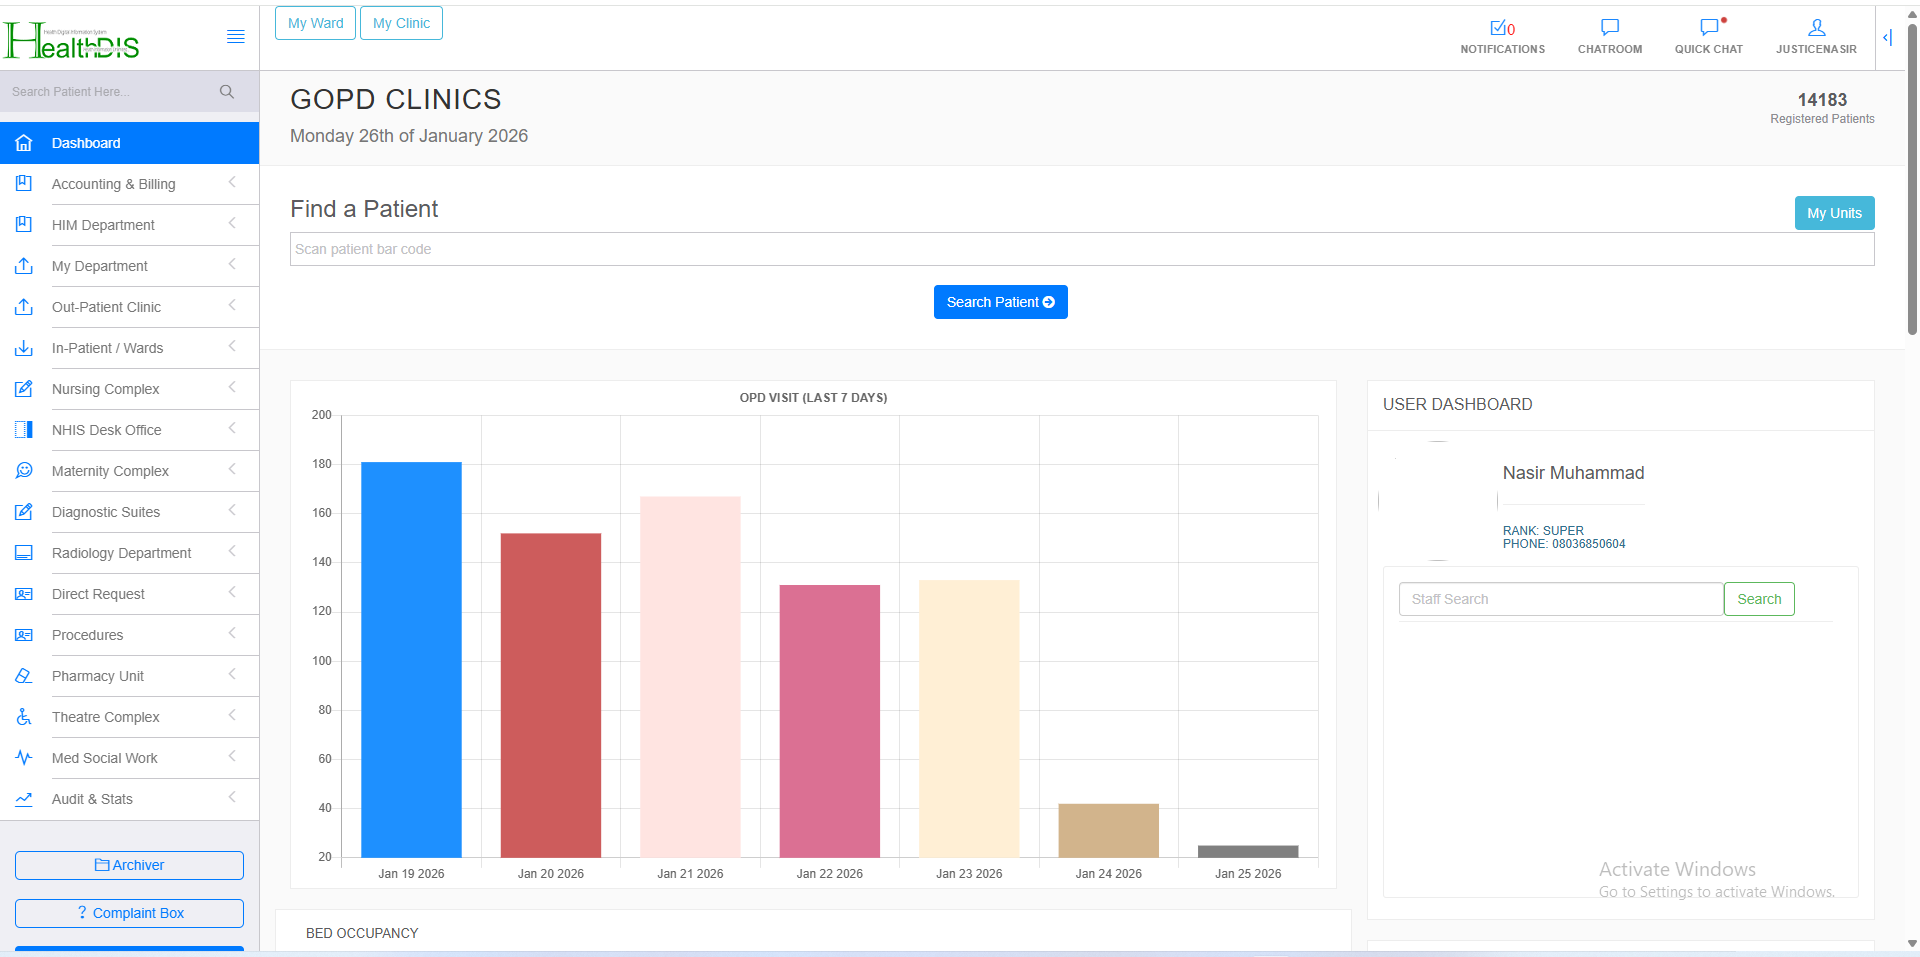

With our EHR, seamlessly manage clinical operations, administrative workflows, and financial services efficiently in one integrated platform.

Request Demo Request Demo

Manage doctors, nurses, pharmacists, and laboratory services efficiently through a centralized clinical system.

Securely accept and manage patient payments with seamless billing and transaction tracking.

Manage financial operations, administrative activities, and system configurations.

Accessing patient diagnosis statistics is easy. Our software tracks all diagnoses and investigations for each patient, allowing you to visit the statistics module and download data for research purposes.

Our software is accessible from your own domain, hosted for you, allowing you to work in real-time with your facility from home.